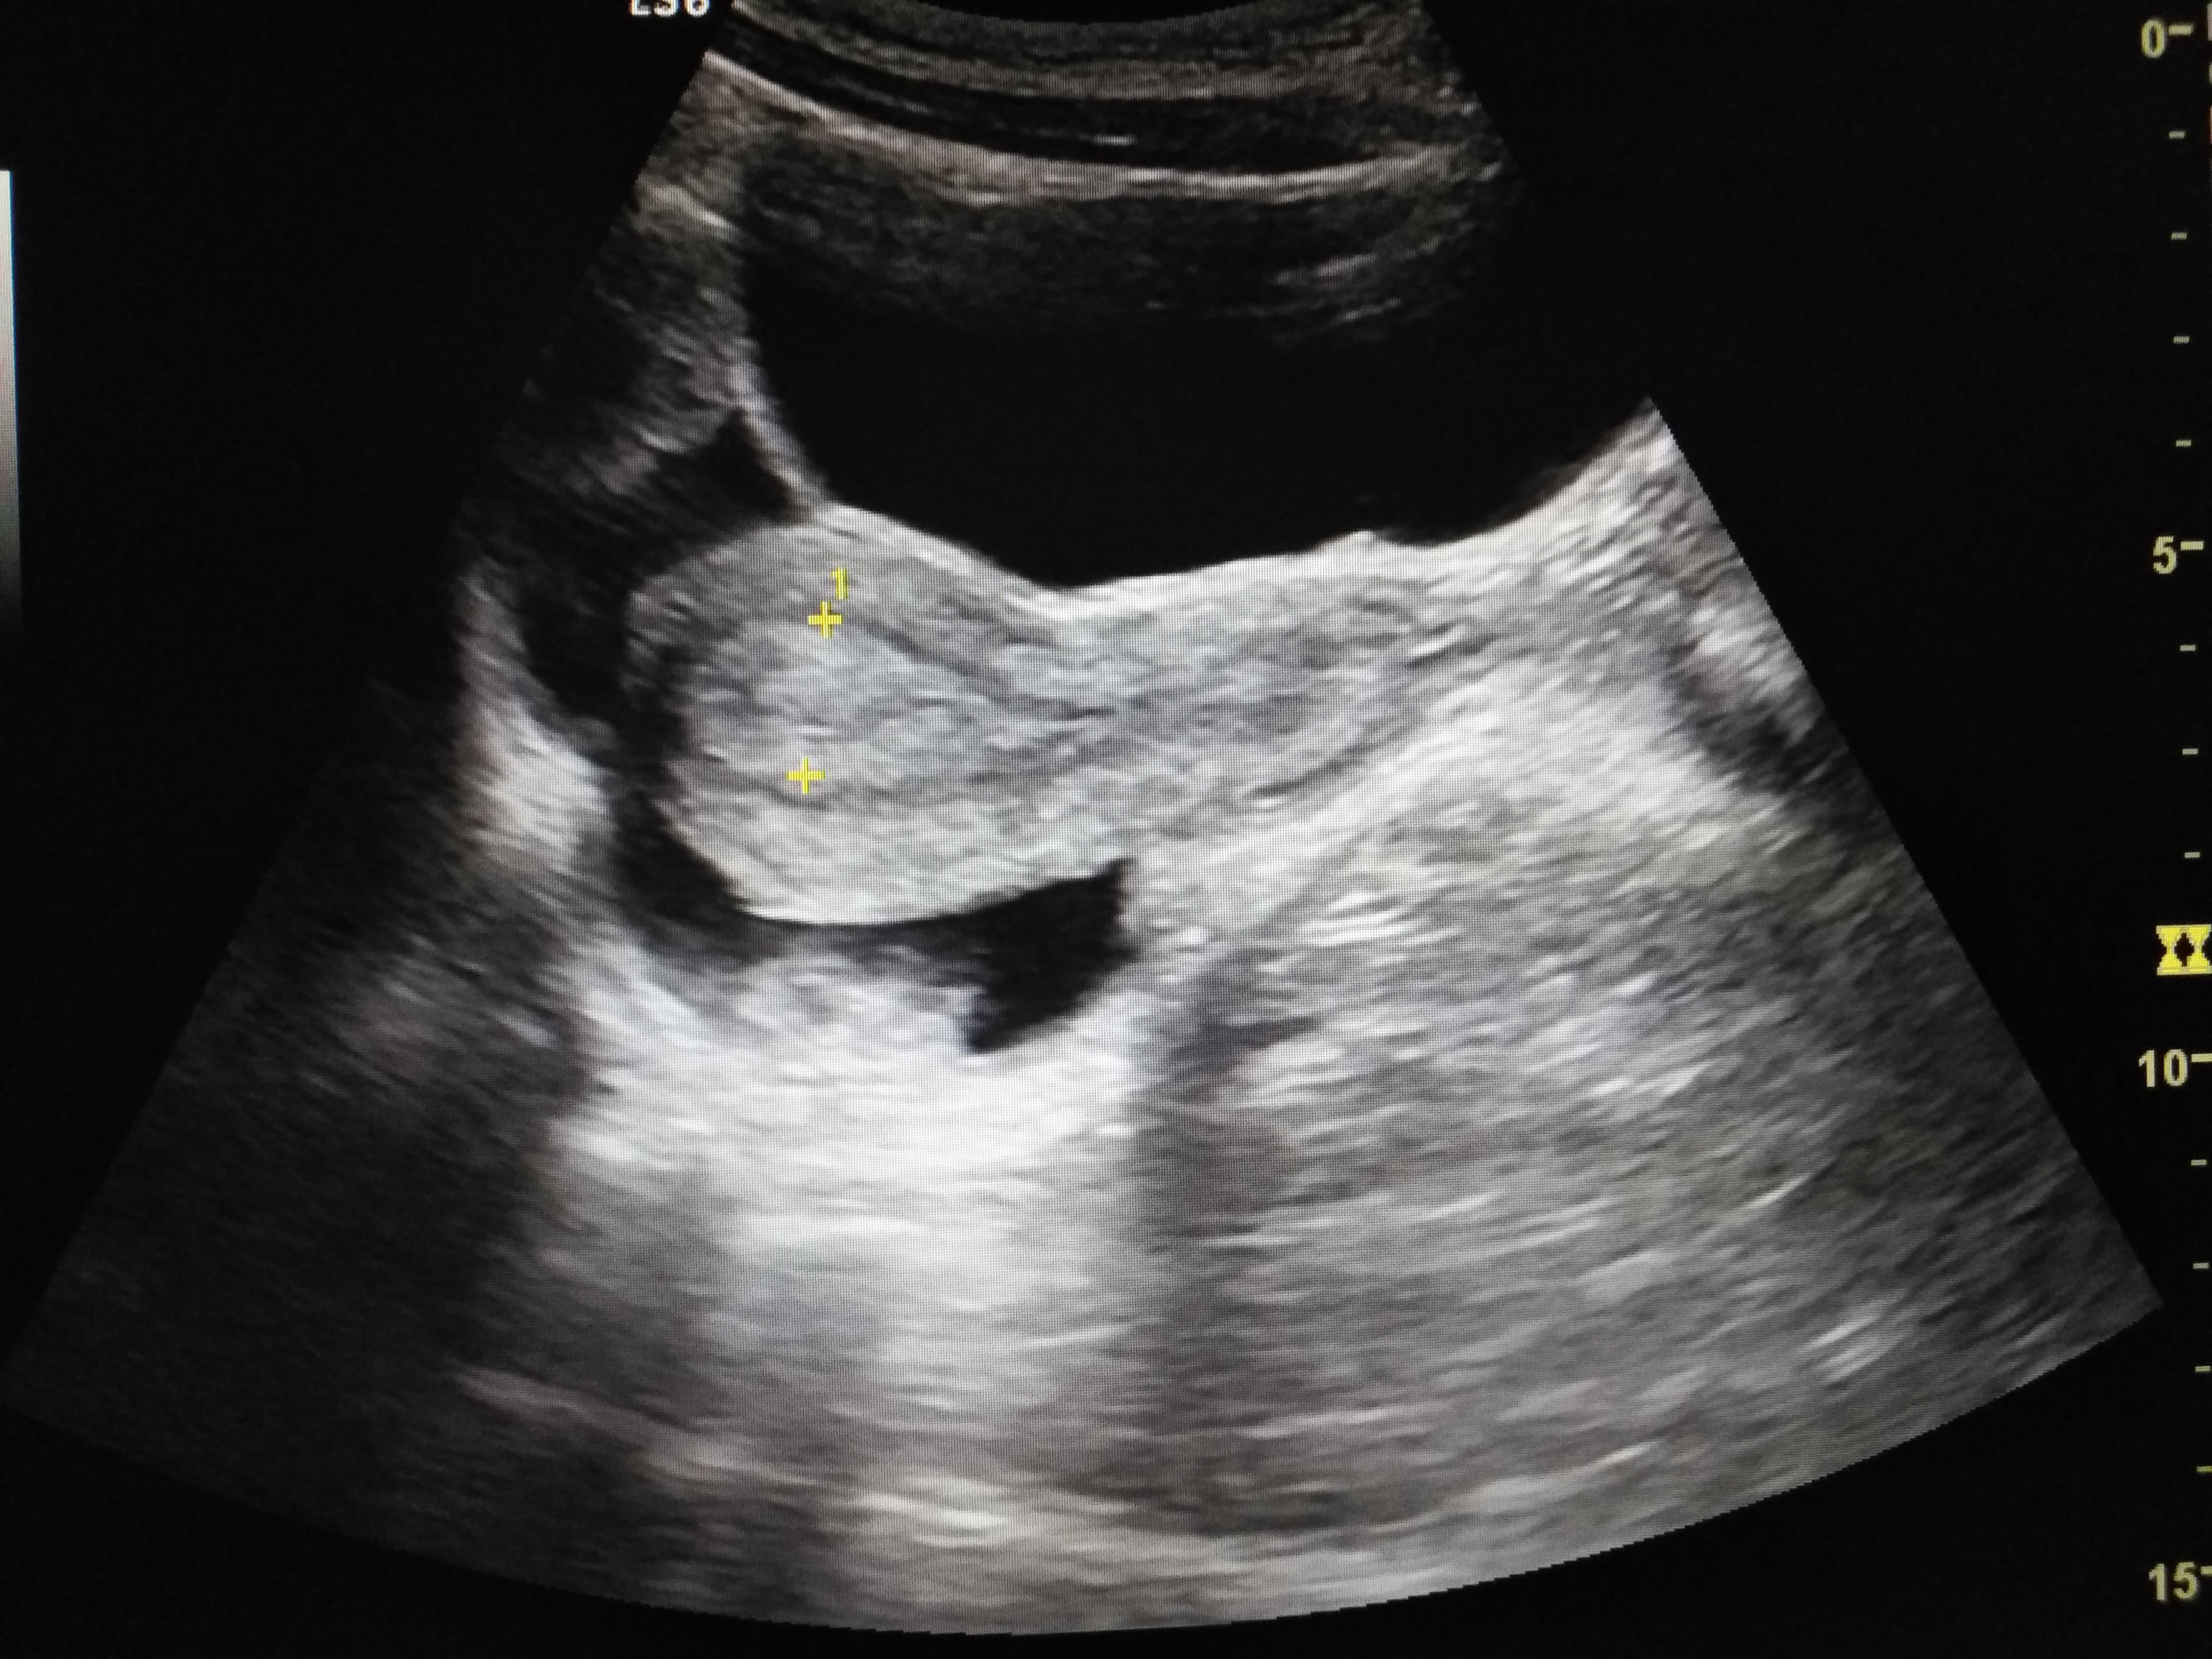

正常子宫附件

图片尺寸720x540